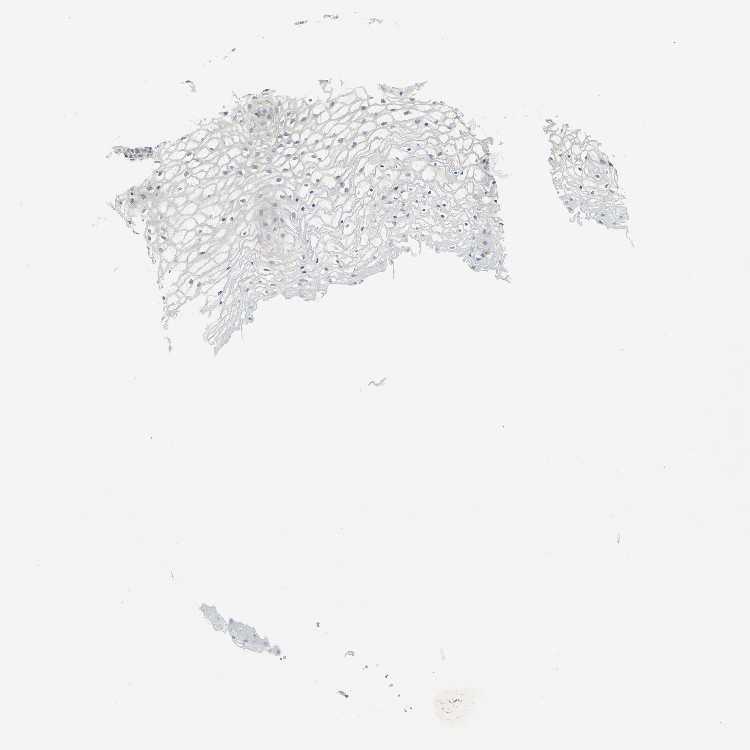

VAGINA - Antibody stainingi

Antibody staining in the annotated cell types in the current human tissue is reported as not detected, low, medium, or high, based on conventional immunohistochemistry profiling in selected tissues. This score is based on the combination of the staining intensity and fraction of stained cells.

Each image is clickable and will lead to virtual microscopy that enables deeper exploration of all samples and also displays staining intensity scores, fraction scores and subcellular localization as well as patient and tissue information for each sample.

Antibody HPA006136

Squamous epithelial cells Low